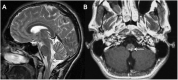

Relapsing demyelinating syndromes (RDS) in children encompass a diverse spectrum of entities including multiple sclerosis (MS) acute disseminated encephalomyelitis (ADEM), aquaporin-4 antibody associated neuromyelitis optica spectrum disorder (AQP4-NMOSD) and myelin oligodendrocyte glycoprotein antibody disease (MOG-AD). In addition to these, there are "antibody-negative" demyelinating syndromes which are yet to be fully characterized and defined. The paucity of specific biomarkers and overlap in clinical presentations makes the distinction between these disease entities difficult at initial presentation and, as such, there is a heavy reliance on magnetic resonance imaging (MRI) findings to satisfy the criteria for treatment initiation and optimization. Misdiagnosis is not uncommon and is usually related to the inaccurate application of criteria or failure to identify potential clinical and radiological mimics. It is also notable that there are instances where AQP4 and MOG antibody testing may be falsely negative during initial clinical episodes, further complicating the issue. This article illustrates the typical clinico-radiological phenotypes associated with the known pediatric RDS at presentation and describes the neuroimaging mimics of these using a pattern-based approach in the brain, optic nerves, and spinal cord. Practical guidance on key distinguishing features in the form of clinical and radiological red flags are incorporated. A subsection on clinical mimics with characteristic imaging patterns that assist in establishing alternative diagnoses is also included.